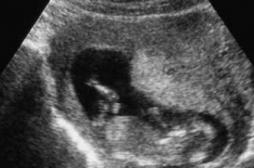

LES MALADIES